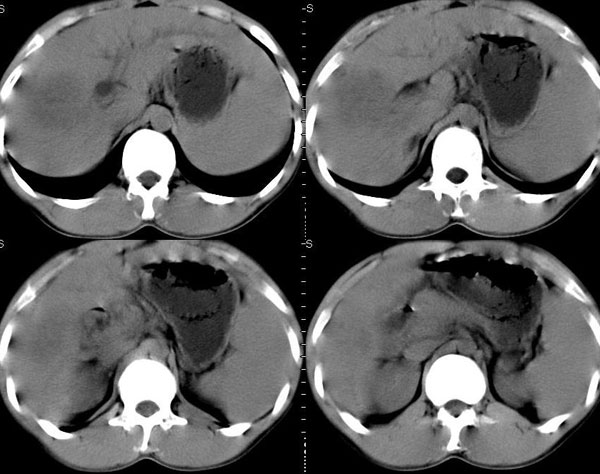

以下是引用晓杰在2006-8-26 21:18:00的发言:[br]肝右叶前段片状低密度灶,边缘模糊。肝内胆管扩张。考虑肝ca? 肝脓肿?[br][br][br]胰头增大,结构模糊,考虑:占位病变。建议增强